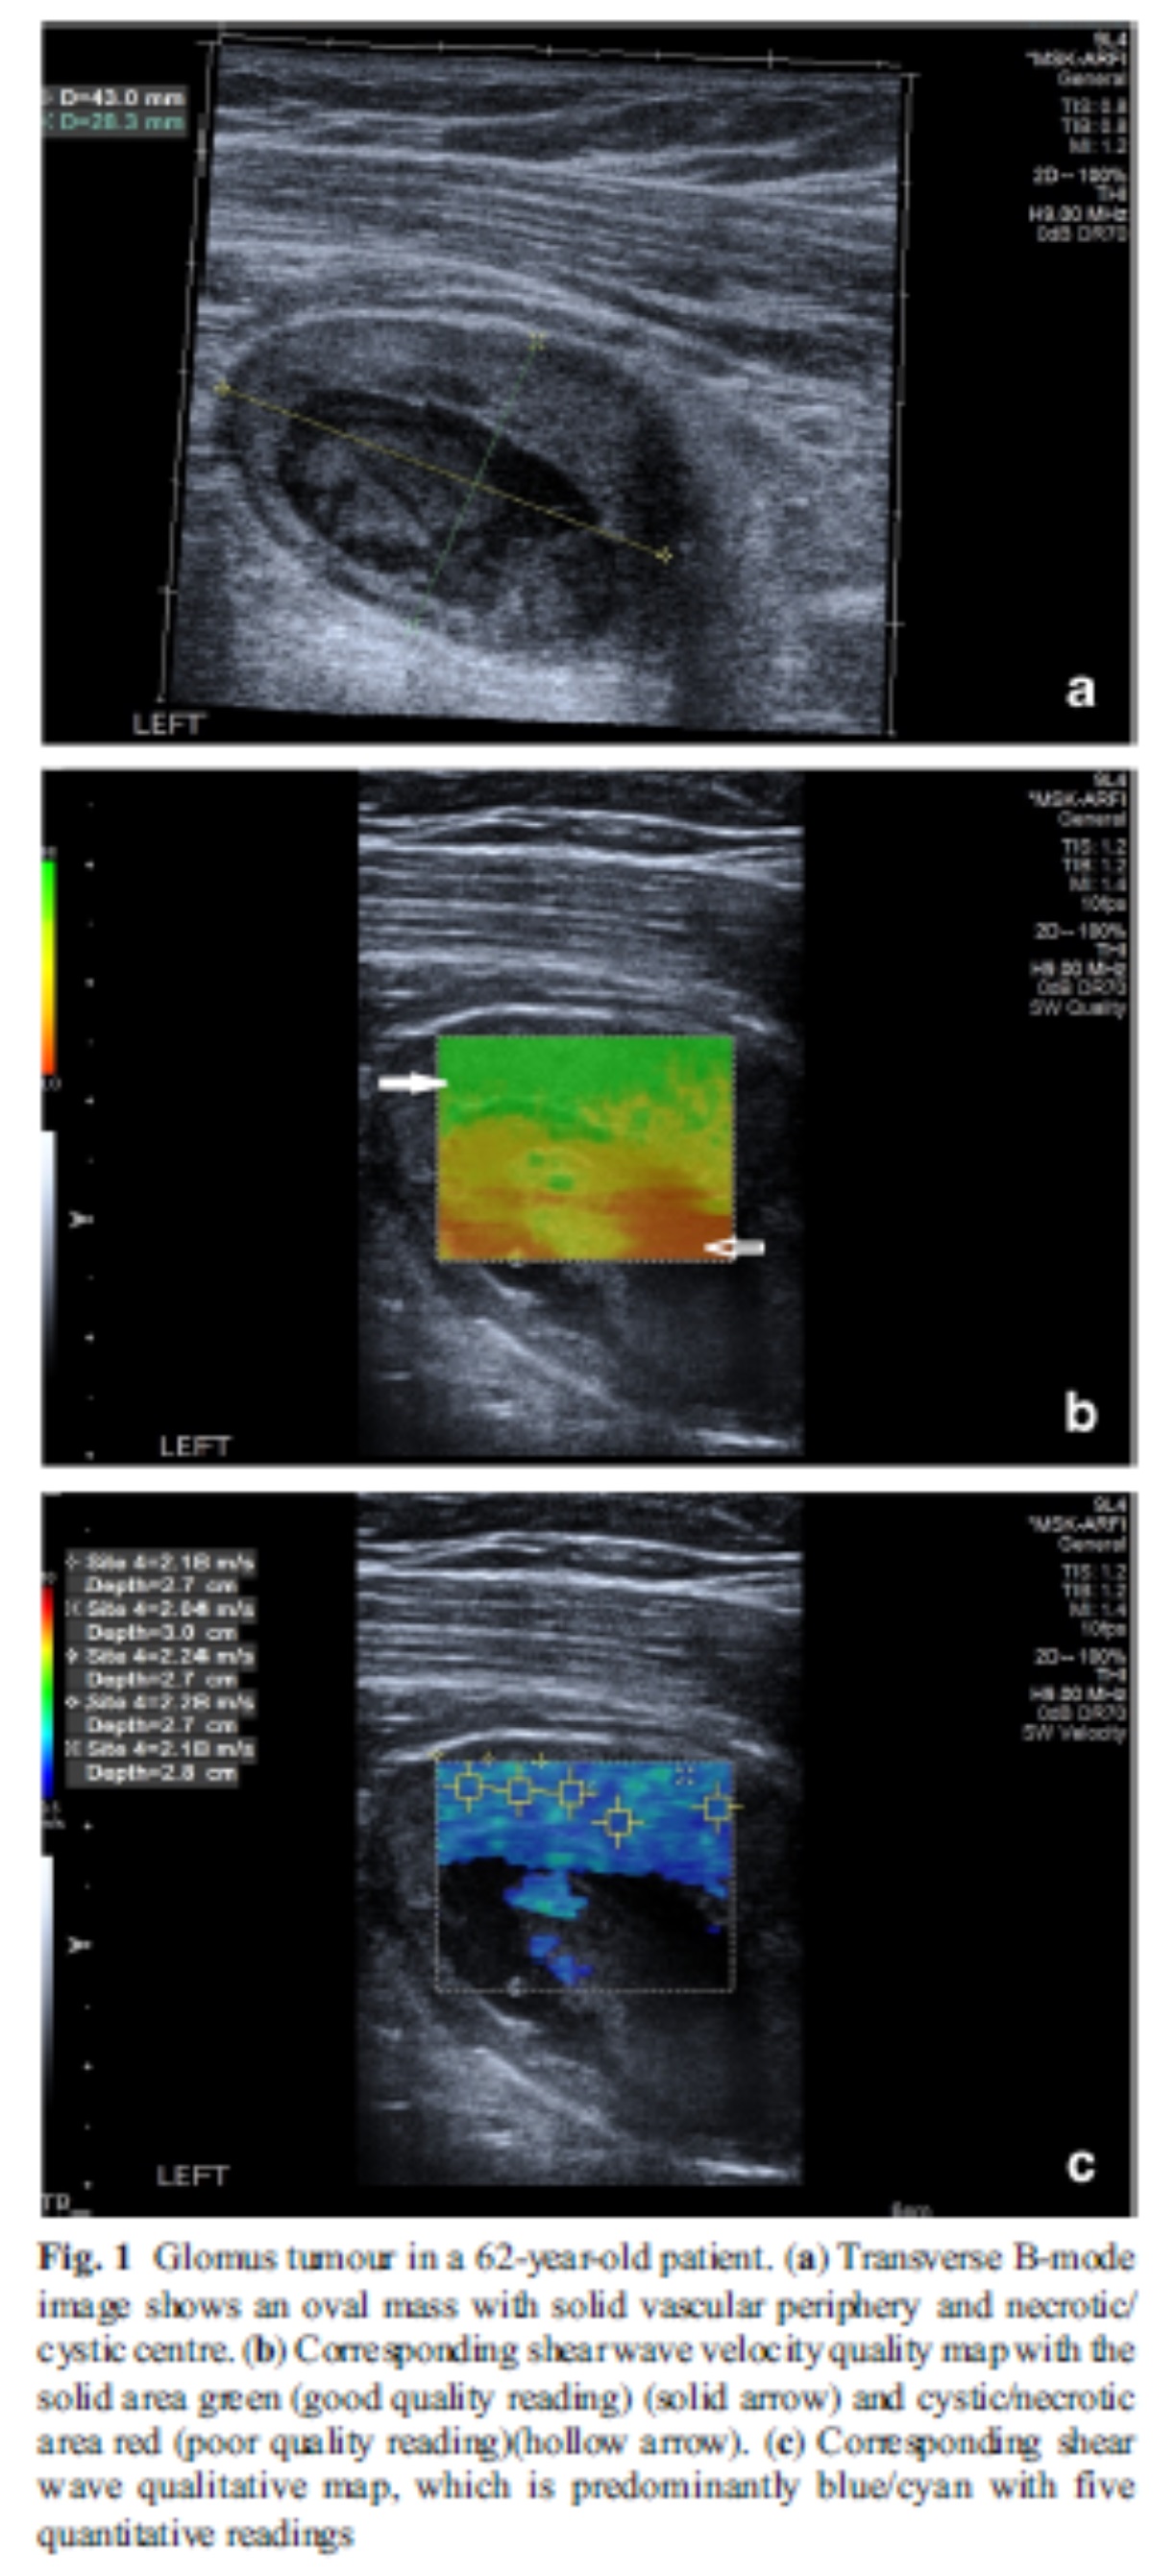

복합적인 성질을 가진 glomus tumor. 중간 사진에서 단단한 고형부분인 위쪽은 파랑에 가깝게, 아래의 부드러운 낭성/괴사성 부분은 빨강에 가깝게 보인다.